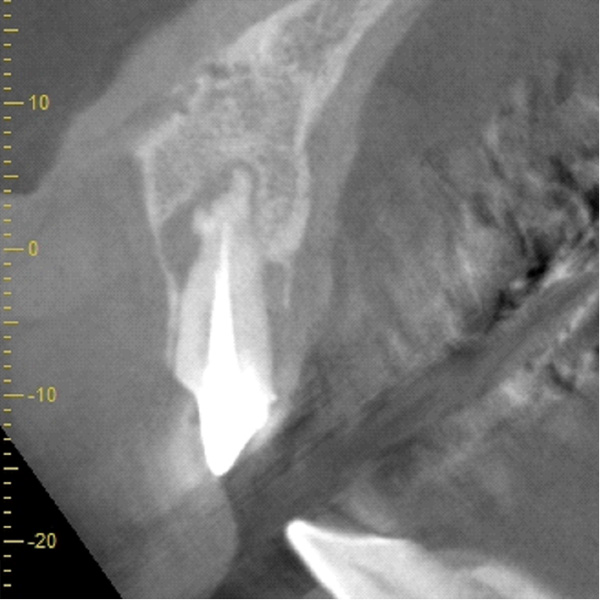

| 年代・性別 | 50代 男性 |

| 主訴 | 前医で前歯を抜かなければならないがインプラントはできないと言われた |

| 治療期間 | 約12ヶ月 |

| 費用 | 600,000円 |

| 治療内容 | インプラント、骨造成、結合組織移植、セラミック修復 |

| 治療に伴うリスク | インプラント周囲炎 セラミックの破折、脱離 |